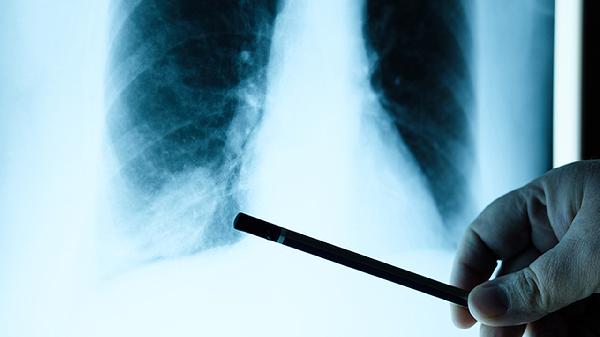

肺部CT怎么区分炎症和癌症

肺部CT区分炎症和癌症主要依据病灶形态、边界特征、生长速度及伴随症状等差异,需结合临床检查和病理结果综合判断。

炎症性病变在CT上多表现为斑片状模糊影或磨玻璃样改变,病灶边缘不规则但周围常见渗出性改变,部分可见支气管充气征。肺炎链球菌感染可能伴随发热、咳嗽等急性症状,结核病灶则多位于肺上叶且易出现空洞。炎症通常对抗生素治疗敏感,2-4周复查可见病灶缩小。肺脓肿表现为厚壁空洞伴液平面,周围有显著炎性浸润。机化性肺炎可见反晕征或沿支气管血管束分布的实变影。

恶性肿瘤多呈现分叶状结节或团块影,边缘可见毛刺征或胸膜凹陷征。腺癌常见磨玻璃成分混合实性结节,鳞癌多表现为中央坏死的不规则肿块。转移瘤多为多发圆形结节,分布于肺外周或胸膜下。肿瘤倍增时间通常为30-400天,PET-CT显示高代谢。部分病例伴随纵隔淋巴结肿大、骨破坏等转移征象。肺泡细胞癌可表现为弥漫性磨玻璃影伴支气管充气征,需与间质性肺炎鉴别。